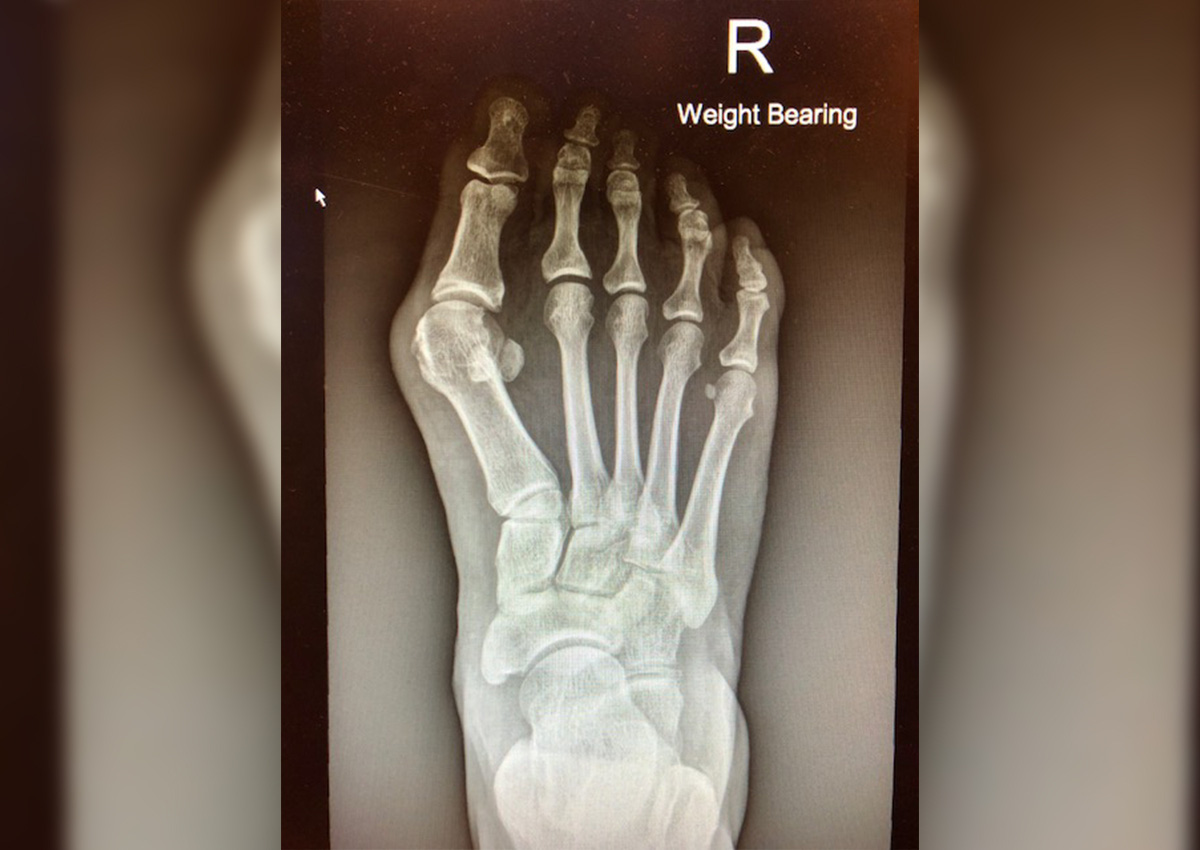

Trên thực tế, "dép lê thực sự giúp giảm các triệu chứng của tình trạng vẹo ngón chân cái (bunion) vì nó không gây nhiều đau đớn cũng như không gây áp lực lớn lên bắp chân như khi chị em thường xuyên phải đi giày cao gót", bác sĩ Tan Ken Jin của phòng khám chỉnh hình và y học thể thao Orthosports giải thích. Vẹo ngón chân cái (bunion) là một biến dạng bàn chân xảy ra ở khớp và xương ngón chân cái, làm cho xương nhô ra. Trong trường hợp nghiêm trọng, các ngón chân chồng lên nhau, gây đau đớn khi mang giày che kín.

Chuyên xử lý các chấn thương và những vấn đề khác liên quan tới bàn chân, 1/3 bệnh nhân của bác sĩ Tan đến gặp anh để điều trị chứng vẹo ngón chân cái, trong đó phần lớn là nữ giới, với tỷ lệ khoảng 8 nữ - 1 nam.

Bạn có biết: Chứng vẹo ngón chân cái có thể do giày dép mà ra

Chứng vẹo ngón chân cái có thể biểu hiện vì lý do di truyền nếu gia đình bạn có thành viên mắc hội chứng này hoặc do cấu trúc bàn chân của bạn. Nó cũng có thể là hậu quả của bệnh gút hoặc các chứng bệnh về chân tiềm ẩn khác.

Mang giày cao gót, mũi hẹp hoặc giày không phù hợp có thể không phải là nguyên nhân của chứng vẹo ngón chân cái, nhưng nó làm tăng nguy cơ mắc hội chứng này cho những người dễ bị.

Các biện pháp điều trị chứng vẹo ngón chân cái

Mặc dù dép lê có thể hữu ích tạm thời trong trường hợp bạn bị vẹo ngón chân cái, nhưng đó không phải là lựa chọn thiết thực nhất. Dép lê cũng chẳng thời trang và bạn không thể đi dép lê tới dự một sự kiện đòi hỏi phải ăn mặc chỉn chu hay thậm chí là đi làm.

Đối với những người bị vẹo ngón chân nhưng không quá nghiêm trọng, có những loại giày với phần mũi giày phù hợp và tấm chắn silicone giúp ngăn ngừa và chặn đứng sự biến dạng ngón chân ở giai đoạn đầu.

Nhưng bạn cũng có thể phải đối mặt với những thay đổi về nếu có nguy cơ bị vẹo ngón chân cái. Trong những trường hợp như vậy, bác sĩ thường khuyên không nên tham gia các môn thể thao như chạy bộ và bóng rổ - chúng gây quá nhiều áp lực lên bàn chân. Ngoài ra, không nên đi giày mũi nhọn và giày cao gót.

Bác sĩ Tan chia sẻ rằng, ngoài các phương pháp điều trị này, không có lựa chọn sẵn có nào khác ngoại trừ phẫu thuật.

Ông cho biết: "Những người có kinh nghiệm hành nghề y sẽ nói với bệnh nhân bị vẹo ngón chân cái rằng, khi tình trạng biến dạng và các triệu chứng của họ trở nên nghiêm trọng, sẽ cần tới một cuộc phẫu thuật truyền thống. Theo đó, bác sĩ sẽ thực hiện một đường rạch mở và sử dụng cưa phẫu thuật để chỉnh sửa tình trạng vẹo ngón chân cái".

Nhưng hiện nay, với một loại phẫu thuật mới - chỉ can thiệp ở mức tối thiểu, bệnh nhân có thể được chỉnh sửa những biến dạng ở chân ngay từ giai đoạn đầu.

Mặc dù có thể đắt hơn một chút, tùy thuộc vào mức độ nghiêm trọng của chứng vẹo ngón chân cái, mỗi ca phẫu thuật cần phải có một bộ mũi khoan mới (mũi khoan phẫu thuật) và toàn bộ quá trình được hướng dẫn bằng tia X. Bác sĩ Tan cũng lưu ý rằng, loại phẫu thuật hạn chế xâm lấn mới này ít gây đau cho bệnh nhân hơn sau phẫu thuật và việc chăm sóc cũng dễ dàng hơn trong vài tháng đầu sau phẫu thuật do vết thương nhỏ hơn. Bên cạnh đó, bạn cũng sẽ không bị sưng phù gì nhiều.